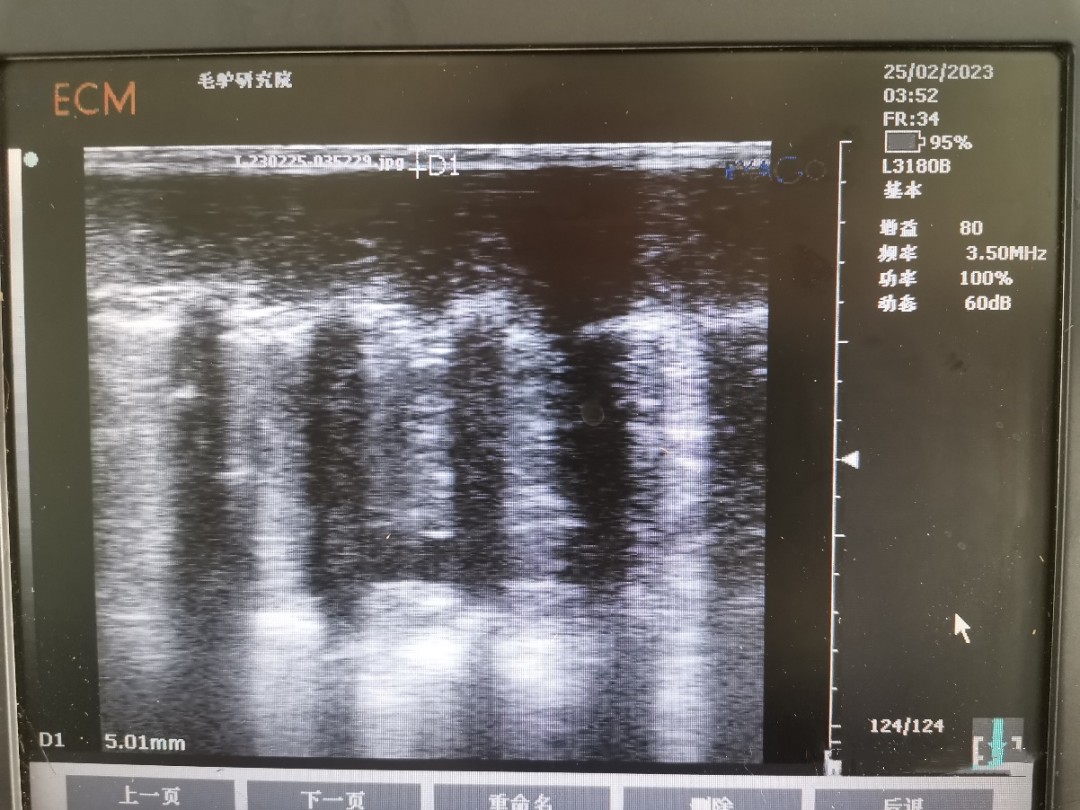

背膘活體測定可反應(yīng)家畜的膘情,而家畜的膘情與繁殖性狀相關(guān)。已有研究表明,豬的背膘和眼肌面積的研究已經(jīng)非常成熟,豬的背膘厚與繁殖性狀相關(guān),眼肌面積與生產(chǎn)性狀相關(guān)。同時(shí),近年來在牛上也陸續(xù)開展背膘和眼肌面積工作的測定。背膘厚度及眼肌面積的活體測定,在指導(dǎo)動(dòng)物的生產(chǎn)、精準(zhǔn)飼喂、動(dòng)物的遺傳改良中發(fā)揮較好作用,使家畜育種和生產(chǎn)工作取得了較大進(jìn)展。但此技術(shù)在驢上應(yīng)用卻較少。

為了彌補(bǔ)背膘和眼肌面積在驢上的應(yīng)用空白,我團(tuán)隊(duì)開展了德州驢背膘和眼肌面積的測定工作。為更好的驗(yàn)證所測定的結(jié)果,團(tuán)隊(duì)成員在已屠宰的德州驢上進(jìn)行確認(rèn),確保測量結(jié)果準(zhǔn)確性。背膘厚及眼肌面積性狀在驢遺傳育種上的應(yīng)用將為選育更加優(yōu)良的德州驢種質(zhì)提供了新的指標(biāo),可加快驢種質(zhì)創(chuàng)新步伐。